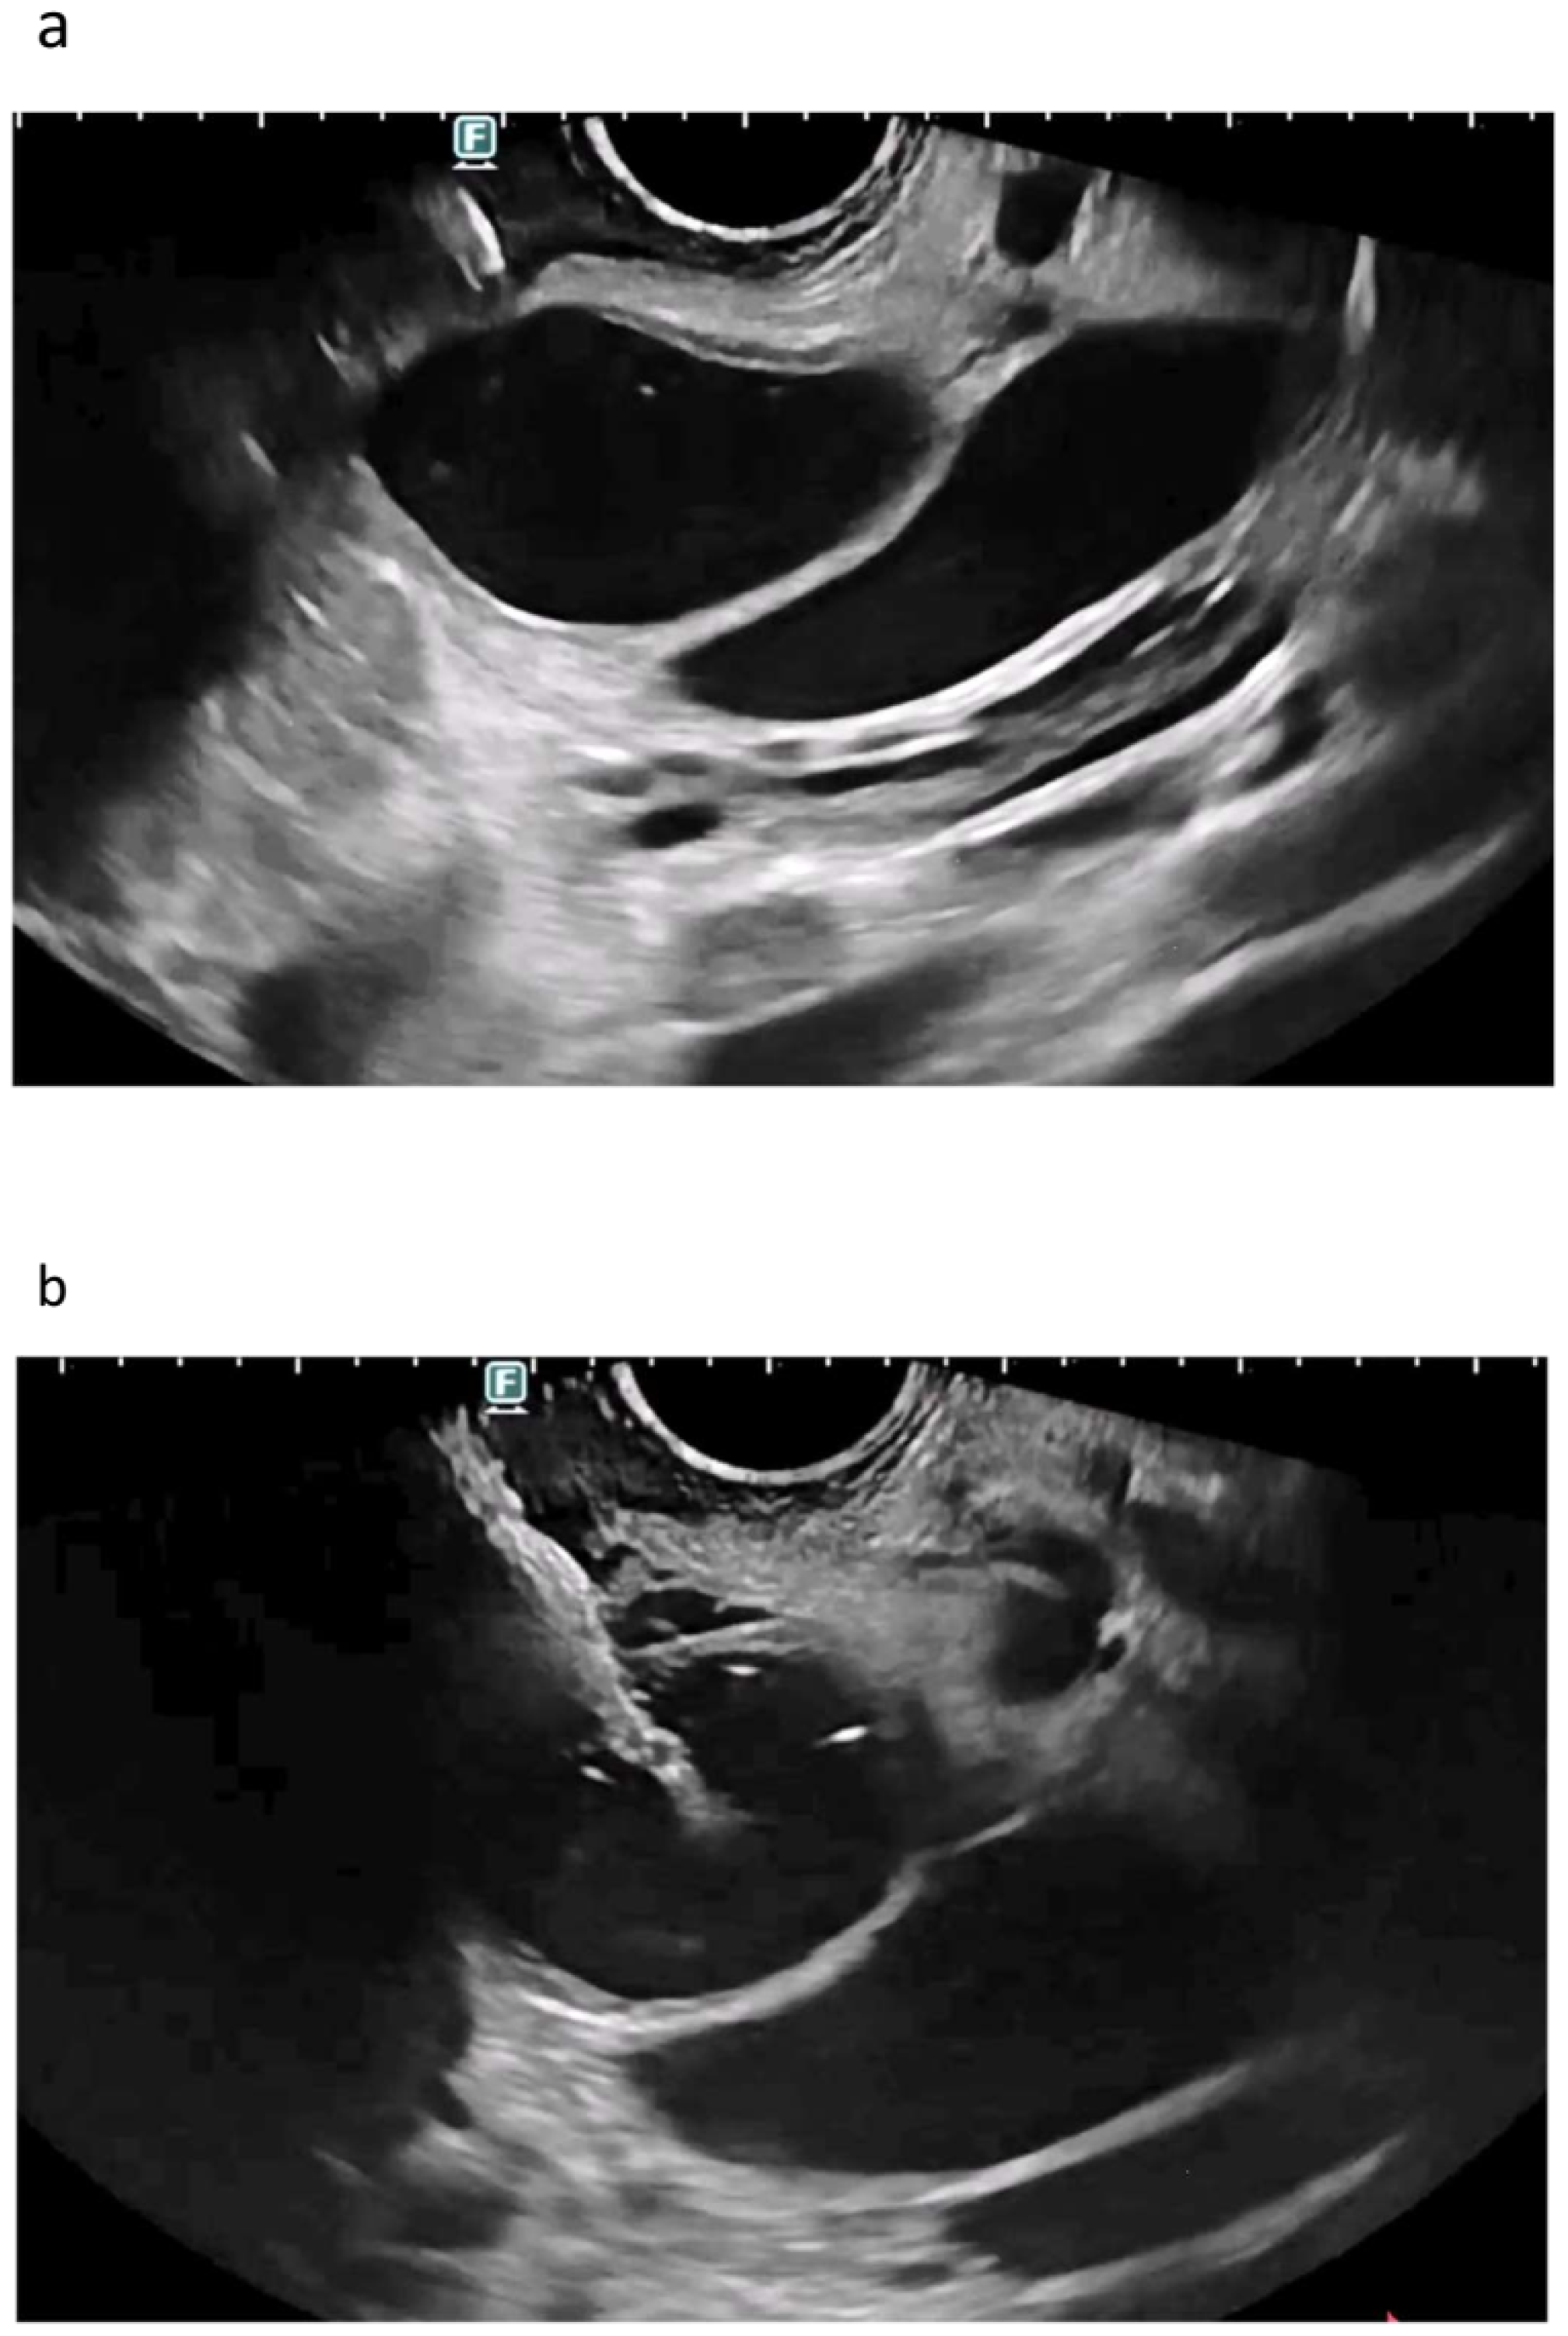

5. Rendezvous Techniques

5.1. Should Rendezvous Be Used First?

5.2. Which Rendezvous Route Should Be Used?